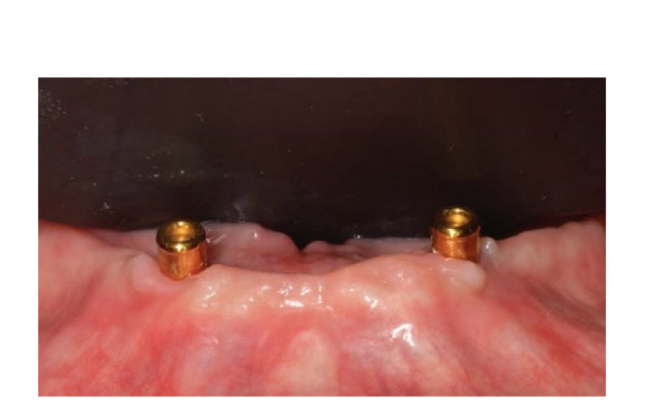

Dopo l'intervento, ai pazienti è stato consigliato di evitare qualsiasi trauma nel sito chirurgico, comprese le procedure di spazzolamento. È stata prescritta una dieta fredda e morbida post-chirurgica. Dopo l'intervento, ai fumatori è stato consigliato di astenersi dal fumo per due settimane. Sono state fornite istruzioni dettagliate per l'igiene orale, inclusa la raccomandazione di sciacquare tre volte al giorno con clorexidina allo 0,12%. Sono stati prescritti analgesici, come 600 mg di ibuprofene o alternative simili, secondo necessità. I punti di sutura sono stati tipicamente rimossi entro un periodo di dieci a quattordici giorni. Secondo un flusso di lavoro precedentemente riportato, le procedure protesiche sono iniziate otto settimane dopo l'inserimento degli impianti. Secondo un protocollo di carico precoce, una nuova dentiera rimovibile completa rinforzata in metallo è stata consegnata in entrambi i gruppi entro quattro settimane dopo l'inserimento degli impianti. Dopo due o tre giorni, gli abutment di guarigione sono stati svitati e gli attacchi sono stati collegati a lato della poltrona alla nuova protesi rimovibile. I pazienti sono stati randomizzati per ricevere attacchi OT Equator® (Rhein’83, Bologna, Italia) nel gruppo di test o attacchi Locator (Zest Anchors LLC) nel gruppo di controllo. I sistemi di attacco randomizzati sono stati posizionati e serrati secondo le istruzioni del produttore. Nel gruppo di test (Figure 1–5), dopo la guarigione gengivale, i più recenti attacchi OT Equator® a basso profilo sono stati avvitati sugli impianti utilizzando il cacciavite quadrato OT Equator®, con un intervallo di coppia di 22–25 Ncm. Le altezze dei manicotti variavano da 0,5 a 7,0 mm, a seconda delle dimensioni della zona di transizione di ciascun impianto, facilmente misurabili utilizzando il misuratore di altezza del manicotto millimetrico a codifica colore (Rhein’83, Bologna, Italia) dopo la rimozione dell'abutment di guarigione. Successivamente, è stato preparato lo spazio necessario per accettare la gabbia in acciaio della sede femminile nella superficie di adattamento della dentiera rimovibile completa mandibolare. Dischi protettivi in silicone (Rhein’83, Bologna, Italia) sono stati posizionati sopra gli attacchi OT Equator®. Cappucci di ritenzione extra-morbidi (giallo, 600 g) sono stati inizialmente inseriti nella sede femminile in acciaio, attaccati a OT Equator®, e infine fissati alla dentiera utilizzando resina acrilica autoindurente. Allo stesso tempo, il paziente ha tenuto le dentiere in occlusione, direttamente a lato della poltrona. Dopo la completa polimerizzazione, la dentiera è stata prelevata e i dischi in silicone sono stati rimossi. L'eccesso di acrilico è stato rifilato e la dentiera è stata rifinita e lucidata. Un mese dopo la consegna delle protesi, i cappucci di ritenzione gialli sono stati sostituiti con un tipo più robusto (rosa, 1200 g).